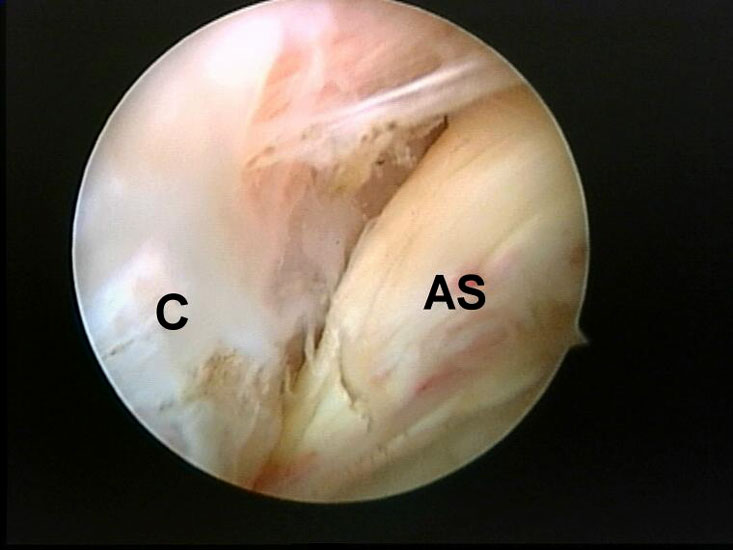

Abbildung 5-7, Video 2

Zunächst wird die Bursektomie (Abb. 5: gerötete Bursa subachillea; C=Calcaneus, B=Bursa, AS=Achillessehne) mit der Radiofrequenzsonde durchgeführt und die Haglundexostose dargestellt. Alternativ kann die Bursektomie mit einem Shaver durchgeführt werden. Hierbei sollte der Ansatz der Achillessehne kaudal einsehbar sein (Abb. 6: C=Calcaneus, AS=Achillessehne) und unbedingt die gesamte mediolaterale Ausdehnung der posterioren Calcaneusfläche erfasst werden (Abb. 7). Häufig liegen Anteile der Exostose weit medial und/oder lateral und werden übersehen.

Abbildung 8, Video 3

Nach vollständiger Darstellung erfolgt die Resektion der Exostose mit einem Acromionizer von medial, wobei auch hier die geschlossene Seite des Arbeitsansatzes zum Schutz der Achillessehne nach dorsal ausgerichtet werden sollte. Verwendet werden können wahlweise Kugel-, Zapfen- oder Walzenansätze mit 3,5-5,5 mm Durchmesser. Ein kleinerer Durchmesser vereinfacht zwar das Handling im engen retrocalcanearen Raum, erfordert aber einen höheren zeitlichen Aufwand als die Verwendung einer höherkalibrigen Fräse. Der Knochenabrieb verstopft dünne Instrumente häufig und der Durchfluss der Spülflüssigkeit ist gering. Es hat sich bewährt, zwei verschiedene Größen bereitzuhalten und ggf. intraoperativ zu wechseln.